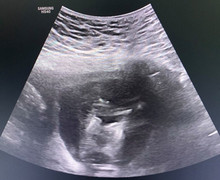

Đây là trường hợp mang 3 thai tự nhiên cùng trứng rất hiếm gặp, chỉ khoảng 1/200.000 ca sinh.